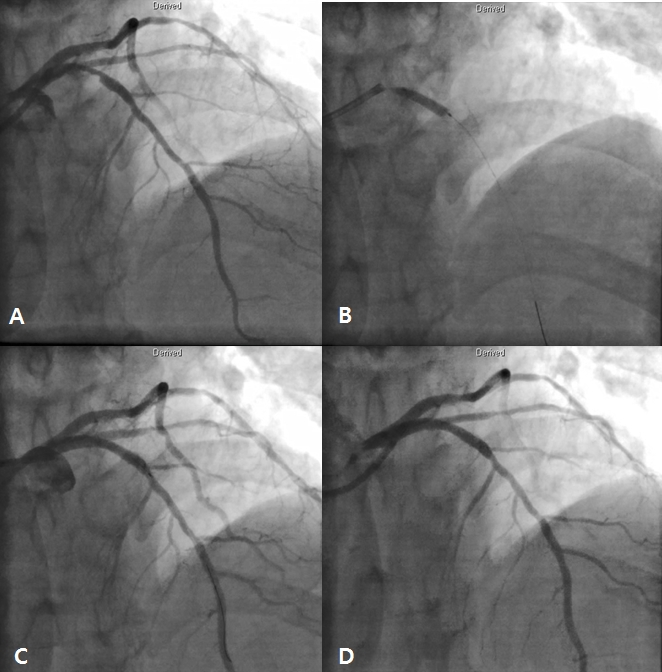

After 3 days later, we performed 2nd stage PCI for proximal LAD. CAG reveled moderate stenosis in proximal LAD (Figure 4A), so we examined optical coherence tomography (OCT) for further evaluation. It showed large amount of plaque (minimal lumen area [MLA] 2.62 mm2) (Figure 5A and 5C). We directly implanted 3.25 and 18 mm everolimus-eluting stent (Xience Alpine®), but follow-up CAG showed mild under-expansion, so we did additional ballooning using 3.25 x 10mm non-complaint balloon (Figure 4B and 4C). Follow-up OCT and CAG showed good distal flow without significant residual stenosis. (post-PCI cross sectional area [CSA] 6.65 mm2) (Figure 4D, 5B and 5D). Because of no-reflow phenomenon for RCA in previous PCI, we performed follow-up CAG and OCT for RCA. CAG and OCT showed stent underexpansion with neointima rupture and large amount of residual thrombi in mid RCA (MLA 2.39 mm2) (Figure 6A, 6B, 7A and 7C). So we did ballooning using 3.25 x 10 mm non-complaint balloon for mid RCA (Figure 6C). Follow-up CAG and OCT showed good distal flow without significant residual stenosis. (CSA 5.03 mm2) (Figure 6D, 7B and 7D). He was discharged without any complications.

Figure 6. Follw-up coronary angiography (CAG) for right coronary artery (RCA) showed mild underexpansion in mid RCA (A). OCT examination for previous stent in RCA (B) and ballooning using 3.25 x 10 mm non-complaint balloon for mid RCA (C). Final CAG showed good distal flow without residual stenosis